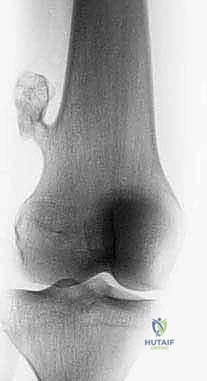

- الأشعة السينية (X-ray): الخطوة الأولى لتقييم العظام وتحديد نمط التدمير العظمي.

- الرنين المغناطيسي (MRI): هو المعيار الذهبي (Gold Standard) لتقييم الأورام. يوضح بدقة امتداد الورم في النخاع العظمي والأنسجة الرخوة، وعلاقته بالأعصاب والأوعية الدموية.

- الأشعة المقطعية (CT Scan): ضرورية لتقييم القشرة العظمية والتكلسات داخل الورم، وللبحث عن أي انتشار في الرئتين.

يعتمد الأستاذ الدكتور محمد هطيف على دراسة هذه الصور الإشعاعية شخصياً قبل تحديد مسار إبرة الخزعة، لضمان عدم تلويث الحجرات العضلية السليمة (Compartments).

الحالة الأولى: إنقاذ ركبة رياضي شاب

شاب يبلغ من العمر 19 عاماً عانى من ألم مستمر في الركبة وتورم لم يستجب للمسكنات. بعد الفحص السريري الدقيق وإجراء الرنين المغناطيسي، اشتبه الأستاذ الدكتور محمد هطيف بوجود ورم. تم إجراء خزعة إبرة أساسية دقيقة جداً. أظهرت النتائج وجود "ساركوما عظمية" في مراحلها الأولى. بفضل الخزعة الدقيقة التي لم تلوث الأنسجة المحيطة، تمكن الدكتور هطيف لاحقاً من استئصال الورم بالكامل وتركيب مفصل صناعي خاص بالأورام، مما أنقذ ساق الشاب من البتر ومكنه من العودة للمشي بشكل طبيعي.